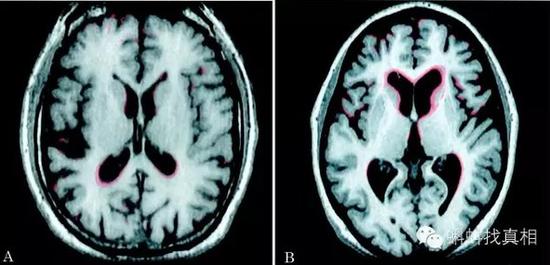

脑萎缩前后对比影像(图片引自微信公众号)

脑萎缩到底是什么呢?准确的说脑萎缩是一种症状,是由各种原因导致脑组织本身发生器质性病变而产生萎缩的一种现象。病理上表现为脑组织体积缩小,细胞数目减少,脑室和蛛网膜下腔扩大。遗传、脑外伤、中毒、脑血管畸形、脑部肿瘤、脑动脉硬化等,任何可以改变脑部血液循环,导致脑组织长期慢性缺血的疾病,都有可能导致脑萎缩。

影像学检查可以发现脑组织体积减少,脑室扩大。初期病人会出现不安、抑郁、偏执、头痛、头晕、失眠、嗜睡、记忆力下降等症状假如脑组织供血得不到改善,病人就会进入病变早期,情感行为明显异常,出现多疑、言语障碍等现象;到了中期即会出现智力减退痴呆等症状;到了后期就完全会瘫痪在床,没有任何行为、辨别能力。